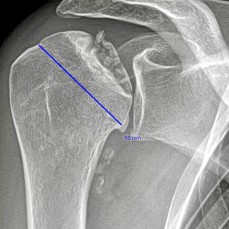

(Bild oben: Durchblutungsstörung Oberarmkopf (Humeruskopfnekrose))